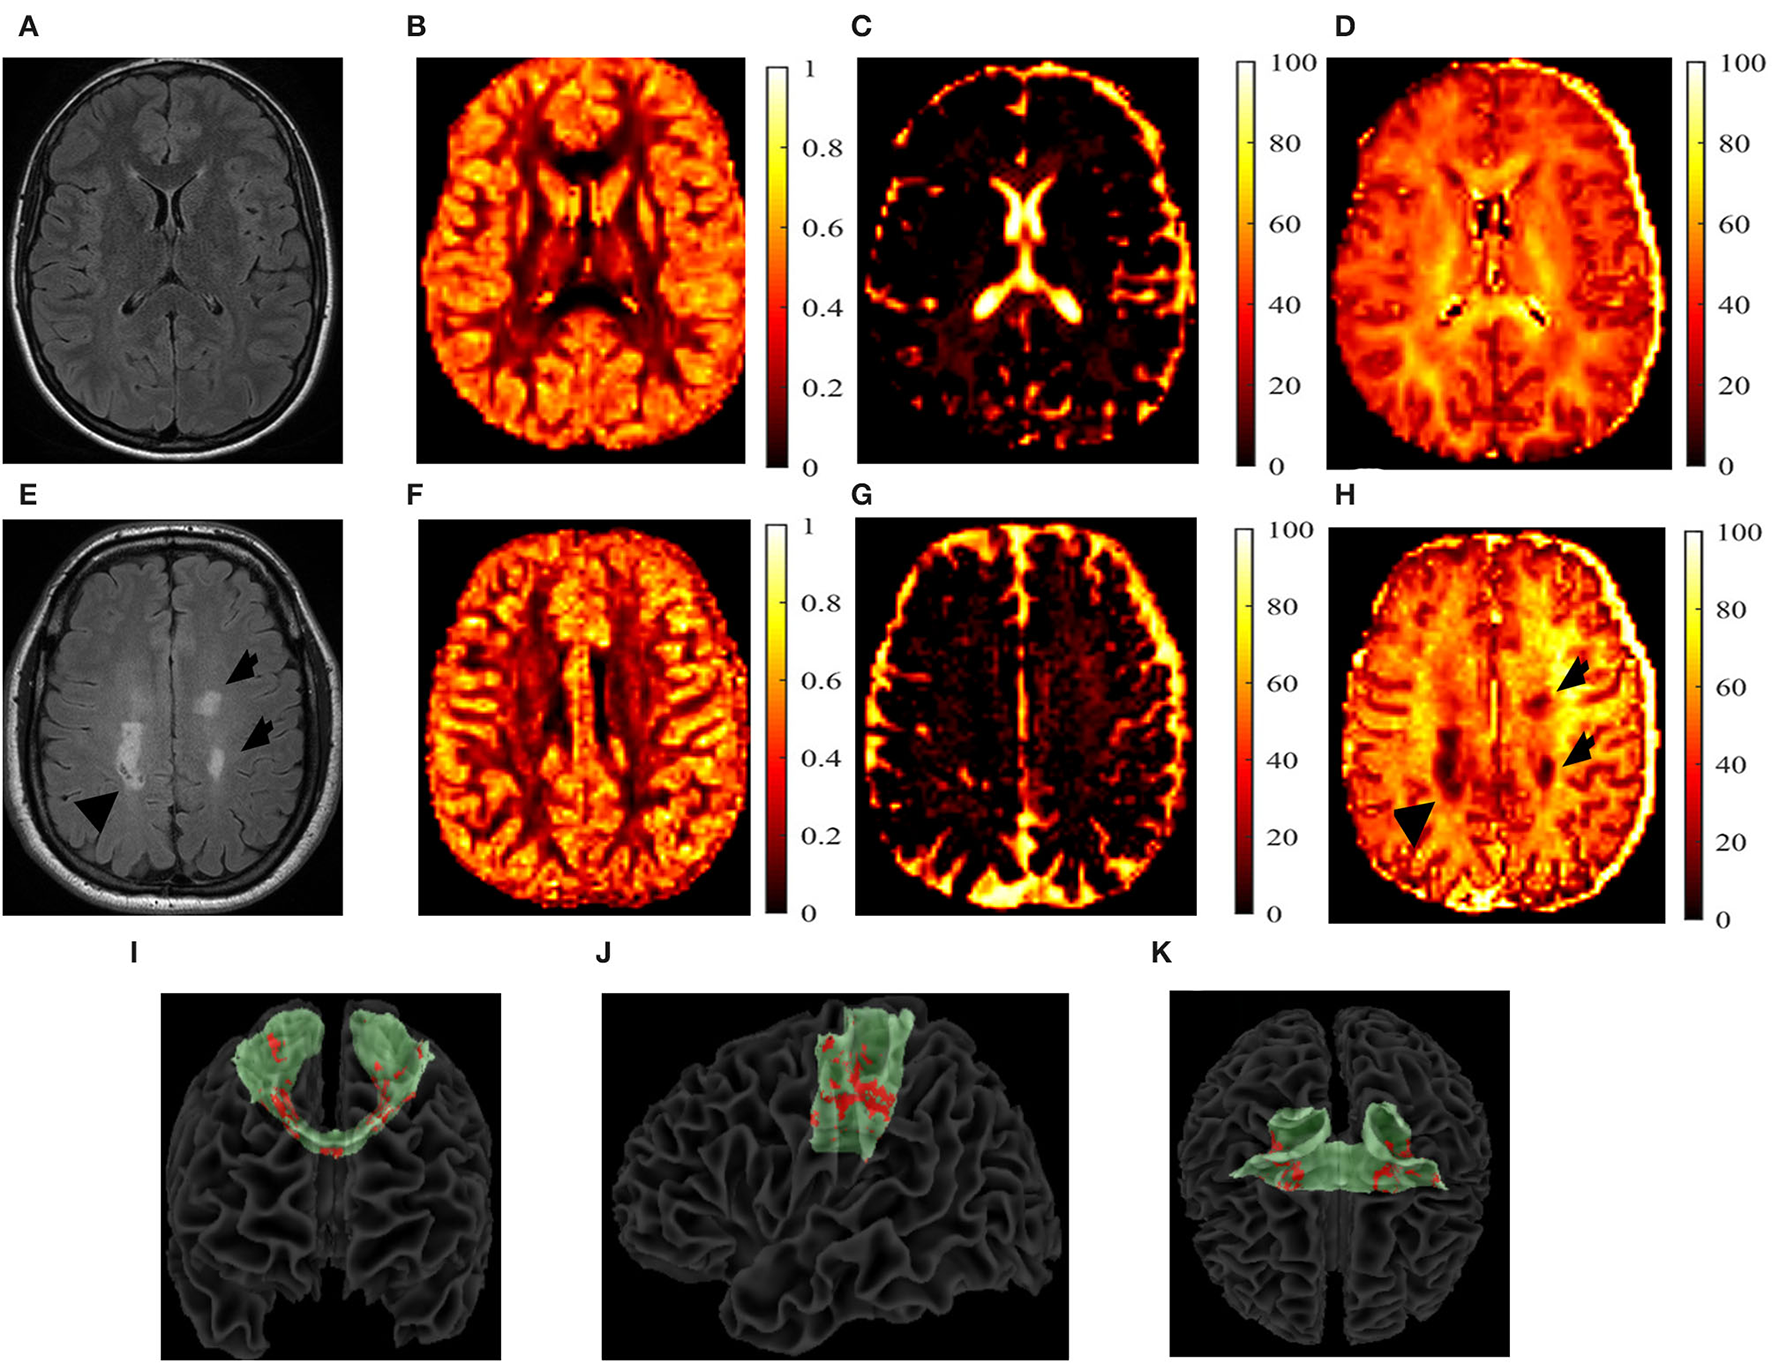

For the pwMS cohort, additional analyses were conducted. First, the chronic black hole lesion masks were used to quantify lesion volumes within each tract. An identical procedure was used for the T2-lesion masks. These masks were subsequently overlaid onto the AD, Vax, and NODDI maps and were summed to calculate tract-specific total lesion loads. From these lesion masks, tract-specific lesional and normal-appearing white matter (NAWM) AD, Vax, IVF, NDI, and ODI measures were calculated and acquired. All of the aforementioned calculations were done using FSL software (version 6.01) (38, 39). Figure 2 shows example of each parametric map in one pwMS and one HC.

Figure 2

T2-fluid-attenuated inversion recovery (FLAIR) images and the neurite orientation dispersion and density imaging (NODDI) parametric maps. T2-fluid-attenuated inversion recovery (T2-FLAIR) images and the neurite orientation dispersion and density index (NODDI) parametric maps of a 27-year-old, white, female healthy control (HC) (A–D) and a 40-year-old white person with relapsing-remitting multiple sclerosis (E–H). The T2-FLAIR (A,E), orientation dispersion index (ODI) (B,F), isotropic volume fraction (IVF) (C,G), and the neurite density index (NDI) (D,H) are shown. T2 lesions are indicated by black arrows. Reconstructed transcallosal fibers of the primary motor cortex are shown in green with both the T1 and T2 lesions shown in red with a coronal (I), sagittal (J), and axial (K) views. I-K show the coronal (I), sagittal (J), and axial (K) views of the reconstructed TC fibers of primary cortex in green, with lesions marked in red of a 56-year-old white male with secondary-progressive multiple sclerosis.